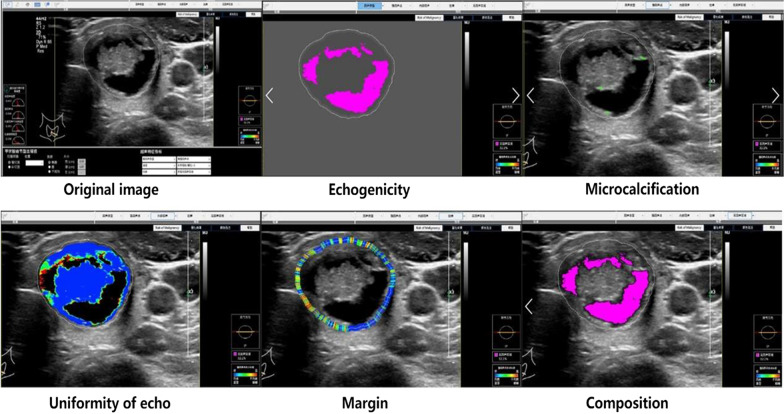

A physician more than 5-year experiences in ultrasound diagnosis marked the anteroposterior diameter and transverse diameter of the original standard images of 296 thyroid nodules with the cursor. Patient data and characteristics were blinded in AmCAD-UT application. Then the computer automatically traced the initial contour of ROI, identified the ultrasound image features of the thyroid nodules, then labeled and quantified the features in different colors, including echo type of the nodules, solid/cystic nature, uniformity of echo, nodular morphology, aspect ratio, and with or without microcalcification (Figs. 1, 2). Finally, the CAD system automatically generated the malignancy risk assessment report and suggestions of thyroid nodules based on 2015 ATA Guidelines [5], 2017 ACR TI-RADS Guidelines [8], 2016 AACE/ACE/AME Guidelines [18] and 2011 Kwak TI-RADS Guidelines [19] in the program.

Fig. 2.

Automatic identification and quantization of ultrasound features of benign thyroid nodules by the AmCAD-UT Detection System